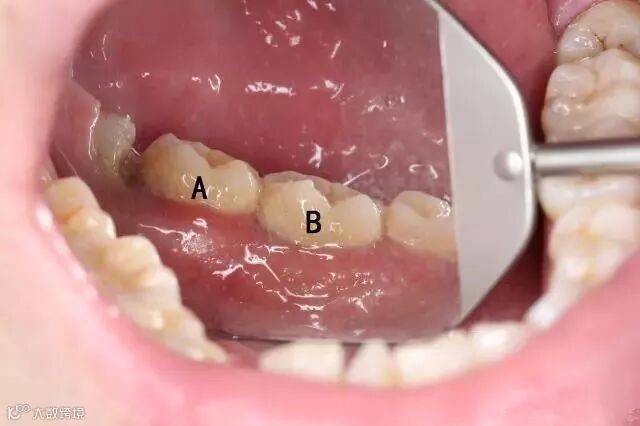

下图标注的A、B两颗牙齿表面看上去都没什么特别严重的问题。

如果我说下图中的牙齿是A、B牙齿中的一颗,你来猜猜是哪颗?

你一定好奇,到底是那颗牙居然这么严重。但是牙齿表面看上去一点问题都没有,对不对?这颗牙其实是上边图中的B牙。

估计很多人都觉得不可思议,这两颗牙看着都没那么脏啊?看着不脏,龈下却已经积满牙结石。而龈下结石可比龈上结石可怕的多,轻则牙龈出血,重则造成牙槽骨吸收,导致牙齿松动脱落等。要知道牙槽骨一旦发生吸收,那就很难再生了,而如果牙槽骨发生了吸收,你觉得牙齿还能稳固吗?